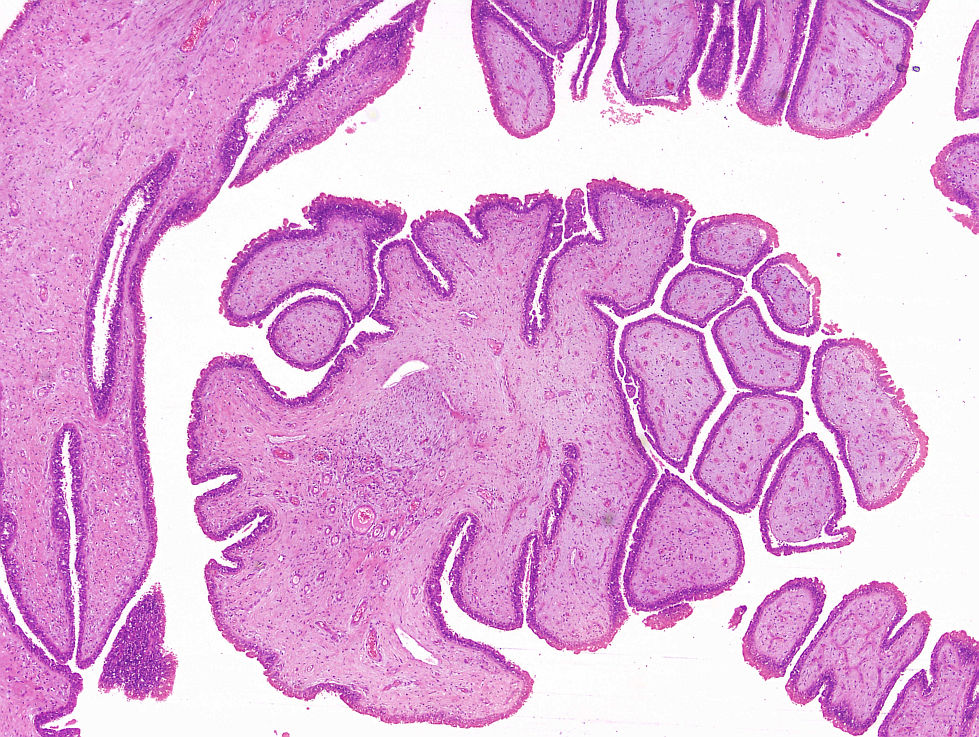

Cas dermatopaotologia. Dona de 36 anys amb pàpules pruriginoses vulvars

Juny 2013